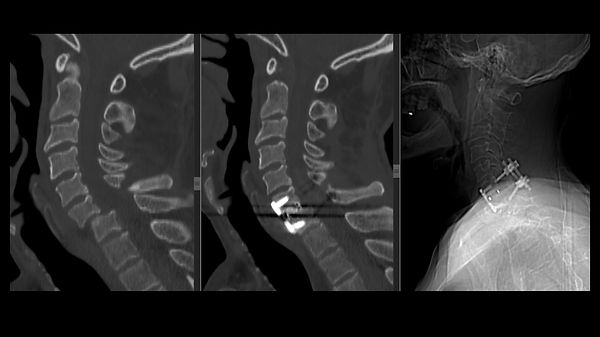

Possono coinvolgere la giunzione cranio-cervicale e le prime due vertebre cervicali (C0-C1-C2) oppure il rachide sub-assiale (C3-C7). Le fratture stabili vengono trattate con collare cervicale tipo Philadelphia a permanenza. Le fratture instabili richiedono un trattamento chirurgico. Per le fratture alte, in base al tipo di frattura, viene effettuata una artrodesi occipito-cervicale, una artrodesi C1-C2 oppure lo screwing del dente di C2 con accesso anteriore. Le fratture del rachide sub-assiale vengono trattate con artrodesi per via anteriore (con cage e placca) o per via posteriore con viti nelle masse laterali. In alcuni casi, per fratture complesse o inveterate, è necessaria una stabilizzazione a 360° con approccio combinato anteriore e posteriore.

Lussazione cervicale traumatica C6-C7